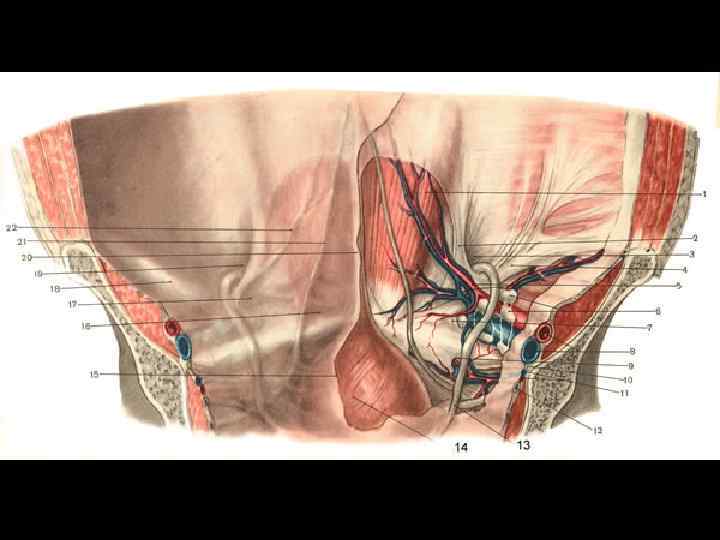

ПАХОВАЯ ГРЫЖА У мужчин – 96 % всех грыж

Паховая грыжа у мужчины Паховая грыжа у женщины

ПРЯМАЯ И КОСАЯ ПАХОВЫЕ ГРЫЖИ

ВРОЖДЕННАЯ И ПРИОБРЕТЕННАЯ ПАХОВЫЕ ГРЫЖИ

ДИФФЕРЕНЦИАЛЬНЫЙ ДИАГНОЗ ПАХОВЫХ ГРЫЖ • Водянка семенного канатика и оболочек яичка • Расширение вен семенного канатика • Липома, киста • Туберкулезный натечный абсцесс • Паховый лимфаденит • Метастаз рака в паховый лимфоузел